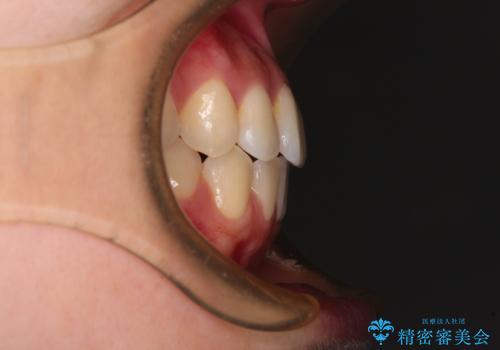

- 前歯のクロスバイトが気になり、インビザラインによる矯正治療を希望して来院された患者様です。

上顎側切歯(上の真ん中から2番目の歯)が舌側転位している場合、インビザラインでは仕上げきれないことが多く、更には無理して動かそうとすると歯髄壊死を起こすリスクが高いと言われています。

インビザラインで歯列を移動する前に、上顎前歯をワイヤー矯正で整え、その後上下歯列をインビザラインにて矯正治療を行うこととしました。

舌側転位している側切歯特有の、切縁の位置が不揃いであったり、根元が内側に引っ込んだ状態であったりという、インビザライン独特の仕上がりになることなく、きれいに整った歯列とすることができました。